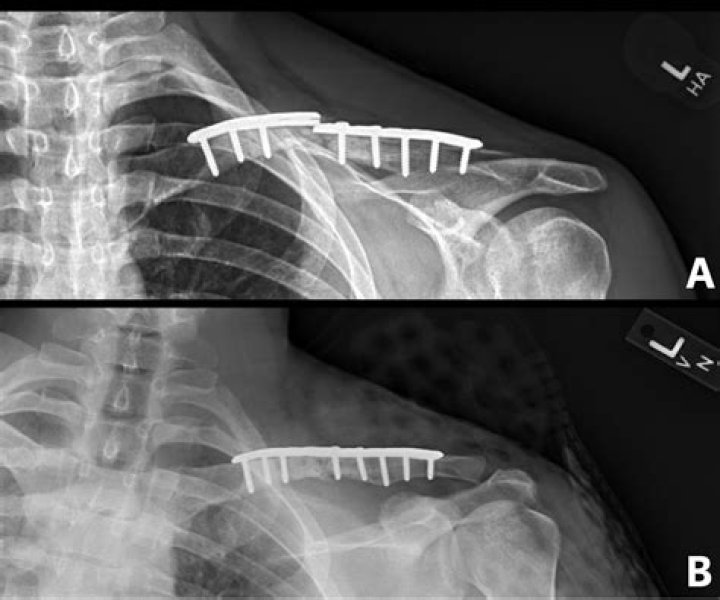

What is clavicle Malunion?

Malunion is when the fracture heals with significant angulation, shortening, and a poor appearance. Mild malunion is common after clavicle fractures, but it is usually not clinically significant. Occasionally, the patient can have pain or a mild limitation in motion or strength.